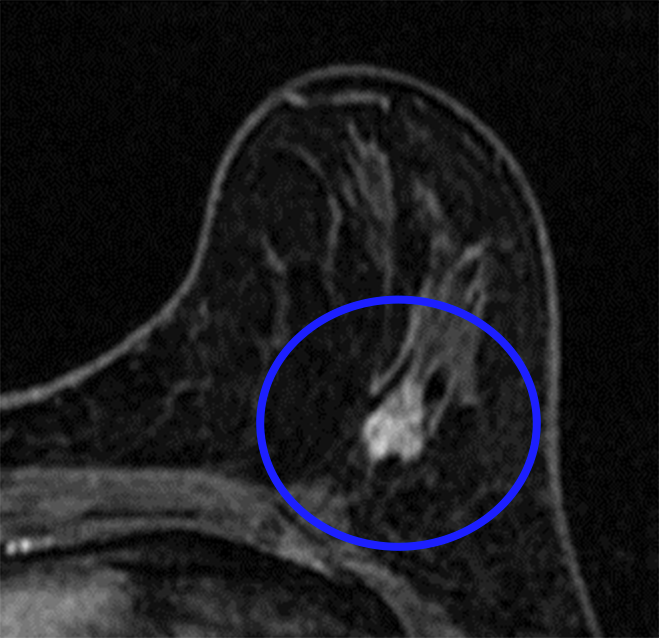

(図2) 術前治療で縮小した乳がん

- (治療前)造影MRI検査

- (治療後)造影MRI検査